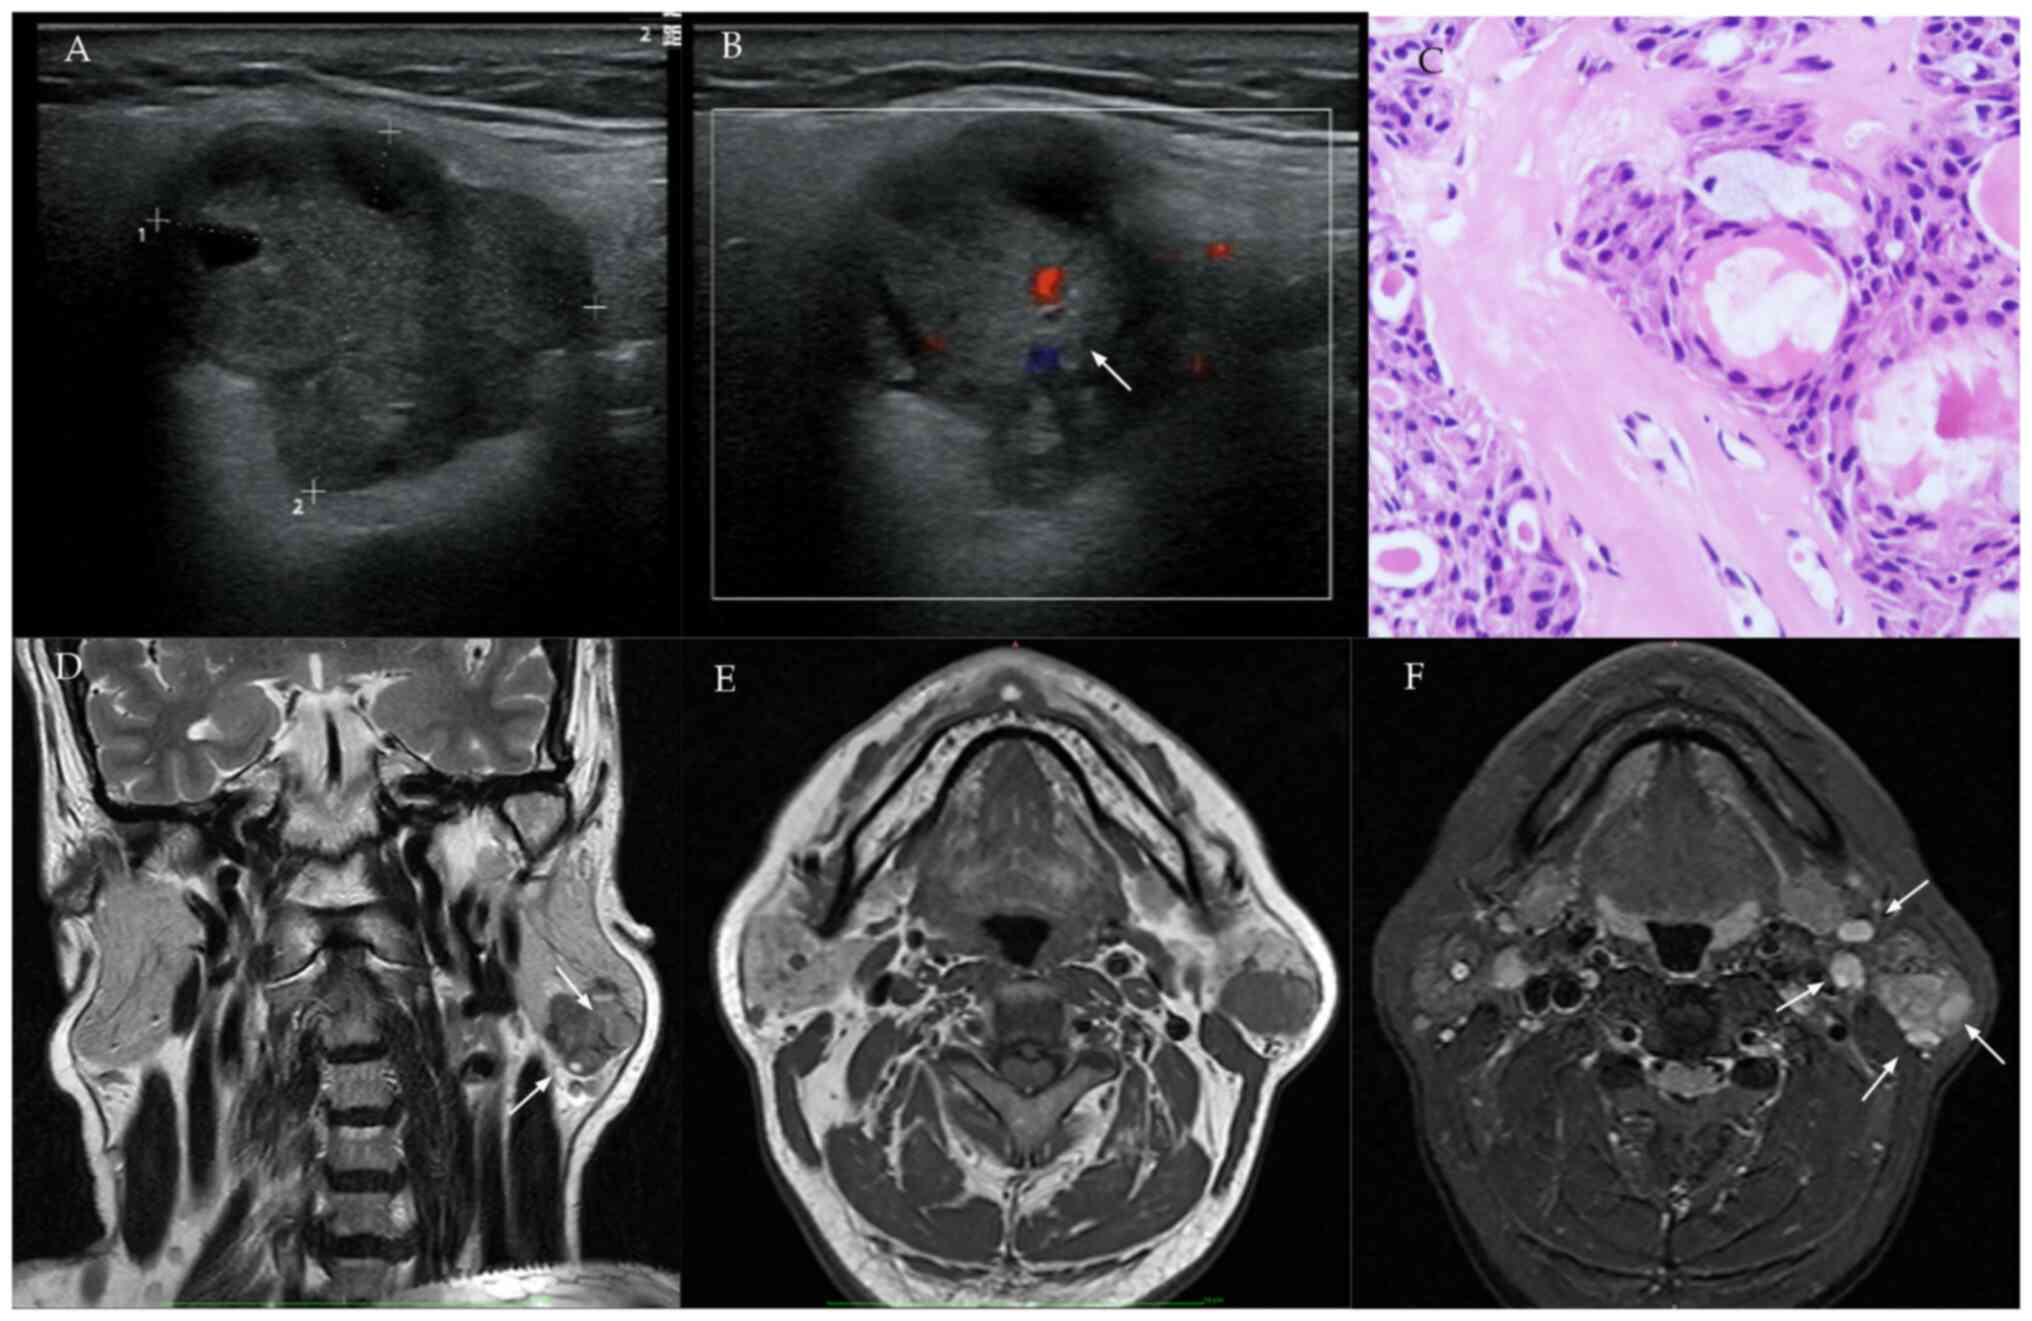

Features of malignant tumor

(mucoepidermoid carcinoma) on US, MRI and histopathology. (A) US

shows an irregularly contoured mass with indistinct margins, marked

hypoechogenicity and pronounced heterogeneity. (B) Color Doppler

demonstrates moderate intralesional vascularity (arrow). (C)

Histopathology (H&E stain): Tumor stroma with dense lymphoid

infiltration, multiple cystic formations and variably distributed

epithelial nests showing squamous differentiation, intermediate

cells and goblet cell metaplasia. (D) Coronal T2-weighted MRI:

Irregular peripheral margins with heterogeneous signal intensity

and nodular components (arrows). (E) Axial T1-weighted MRI:

Homogeneous hypointensity (relative to parotid gland parenchyma).

(F) Short Tau Inversion Recovery sequence: Diffuse signal

heterogeneity with enlarged cervical lymph nodes (arrows). US,

ultrasound.

Figure 2

Features of malignant tumor (mucoepidermoid carcinoma) on US, MRI and histopathology. (A) US shows an irregularly contoured mass with indistinct margins, marked hypoechogenicity and pronounced heterogeneity. (B) Color Doppler demonstrates moderate intralesional vascularity (arrow). (C) Histopathology (H&E stain): Tumor stroma with dense lymphoid infiltration, multiple cystic formations and variably distributed epithelial nests showing squamous differentiation, intermediate cells and goblet cell metaplasia. (D) Coronal T2-weighted MRI: Irregular peripheral margins with heterogeneous signal intensity and nodular components (arrows). (E) Axial T1-weighted MRI: Homogeneous hypointensity (relative to parotid gland parenchyma). (F) Short Tau Inversion Recovery sequence: Diffuse signal heterogeneity with enlarged cervical lymph nodes (arrows). US, ultrasound.